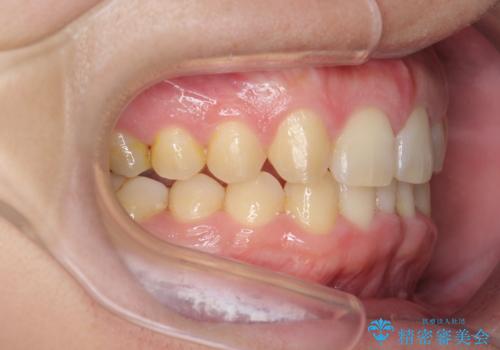

前歯のすき間 歯のがたつき

- 前歯のすき間とがたつきを主訴に来院。

右上の前歯は過去にがたつきがあったとのことで抜いてしまっていました。

歯の数を合わせるために、下の歯を1本抜いて矯正しています。

下の前歯を抜歯したことでブラックトライアングルができましたが、仕上げにIPRを加えることで目立たなくすることができました。